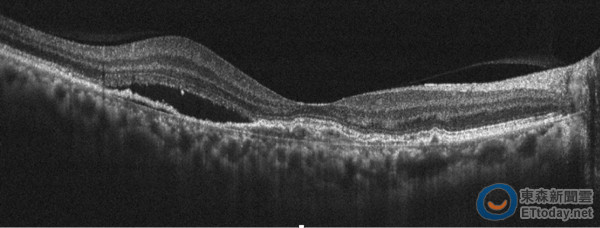

▲眼底斷層掃描可見黃斑部積水。(圖/台北榮總提供)

一名60歲女性,近一周總覺得視力模糊,看電視單手遮眼,還發現右眼看不到。就醫後發現視力僅存0.3,視網膜有橘紅色息肉狀血管瘤,合併有黃斑部水腫,經非侵入性光學共軛斷層血管掃描儀診斷為「老年性黃斑性病變亞型——多足型脈絡膜血管病變」,以光動力療法合併多次眼內藥物抗血管內皮生長因子注射後,視力進步到0.6,黃斑部積水完全恢復。

為快速確診,臺北榮總眼科部於2014年引進「非侵入性光學共軛斷層血管掃描儀(OCT angiography)」,不需散瞳、打顯影劑,只要光學掃描,可即時獲得視網膜斷層及血管影像,對人體傷害少,將視網膜疾病檢查帶入非侵入性檢查的年代。在50例老年性黃斑部病變病患中,針對其中31例多足型脈絡膜血管病變的病患,利用非侵入性光學共軛斷層血管掃描儀,診斷率高達九成,惟眼睛無法固定注視或視網膜大量出血者則不適用。